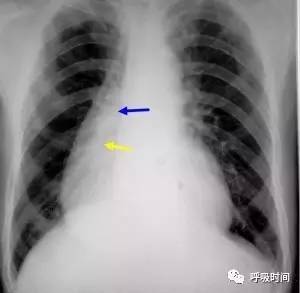

图 23 申请单提供的病情资料:男,44 岁,胸痛 2 天

原诊断:心脏增大。审报告发现,透过增大的「心影」可以看到右侧肺门(蓝箭)及下肺动脉影(黄箭)。

询问病史,患者为食管癌术后。服钡后清楚显示,为胸腔胃(白箭)导致假性心脏增大。